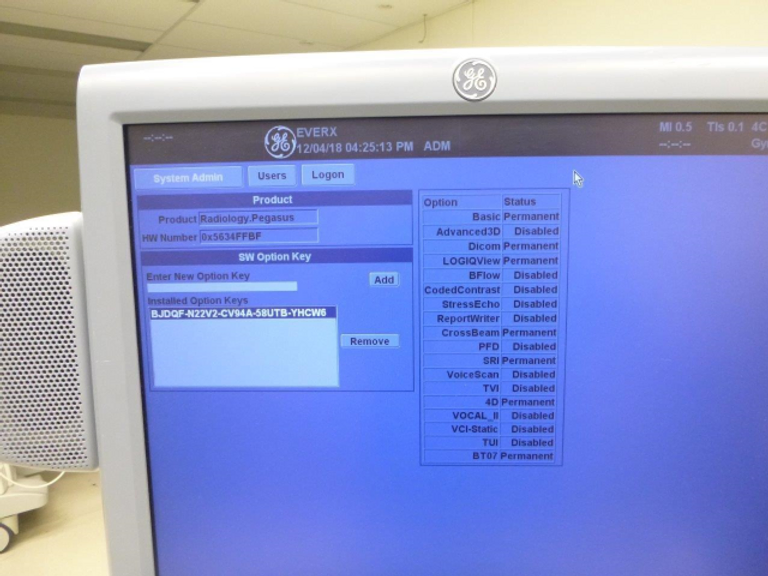

- User-Friendly Design: Designed with user comfort and efficiency in mind, the Logiq 7 features a intuitive touch-screen interface and ergonomic construction, ensuring ease of use for clinicians during diagnostic procedures.

- Seamless Data Management: Benefit from convenient image archiving options, including storage to CD, MOD, or hard drive, enabling efficient data management and access to diagnostic records.